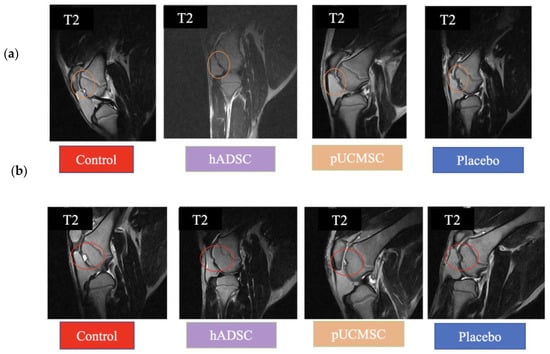

3.1. MRI and CT Observations